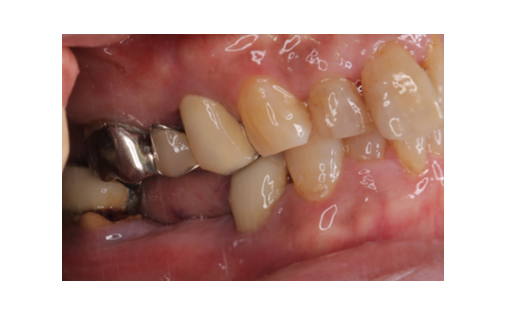

骨造成とインプラント

下顎の骨量が乏しいため骨造成をし、その後インプラント治療を行いました。

かみ合わせも良好でしっかりと機能しています。